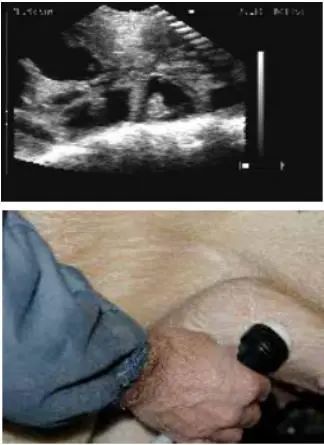

2.4 不同位置的扫描影像图

用B超进行妊娠鉴定时,应检测母猪身体的不同部位,以获得子宫内的详细情况,不同位置的扫描影像见图1、图2、图3、图4和图5。

图 3 位置3超声波影像图